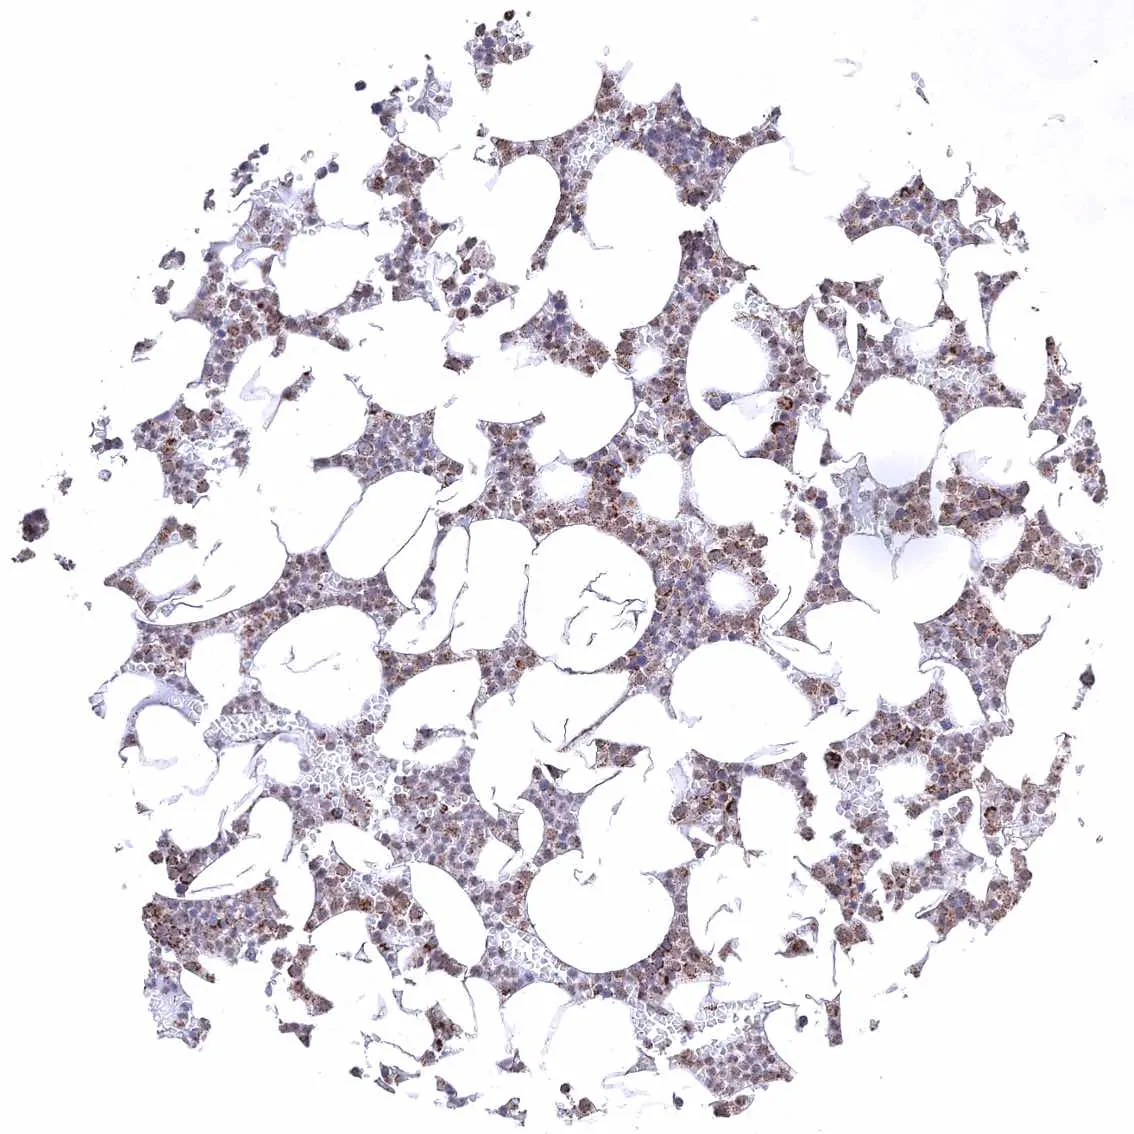

Bone marrow – Cytoplasmic ATP5J staining of variable intensity in all cell types.